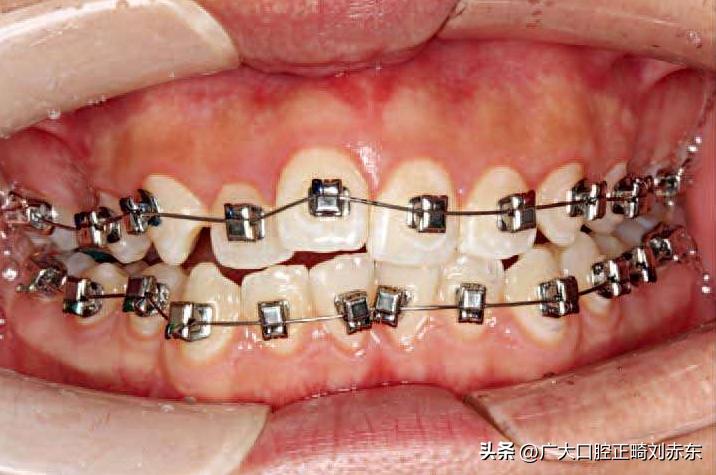

图为使用固定矫治器排齐,持续性施加矫治力